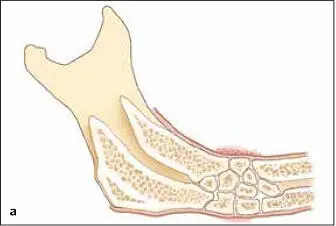

FIG 1-16 (a and b) At about 6 weeks, the graft begins a major resorption-remodeling cycle in which osteoclasts resorb the disorganized immature bone and release BMP and insulinlike growth factors, thus inducing formation of new bone that will mature during function. (Reprinted with permission from Marx and Garg. 1)